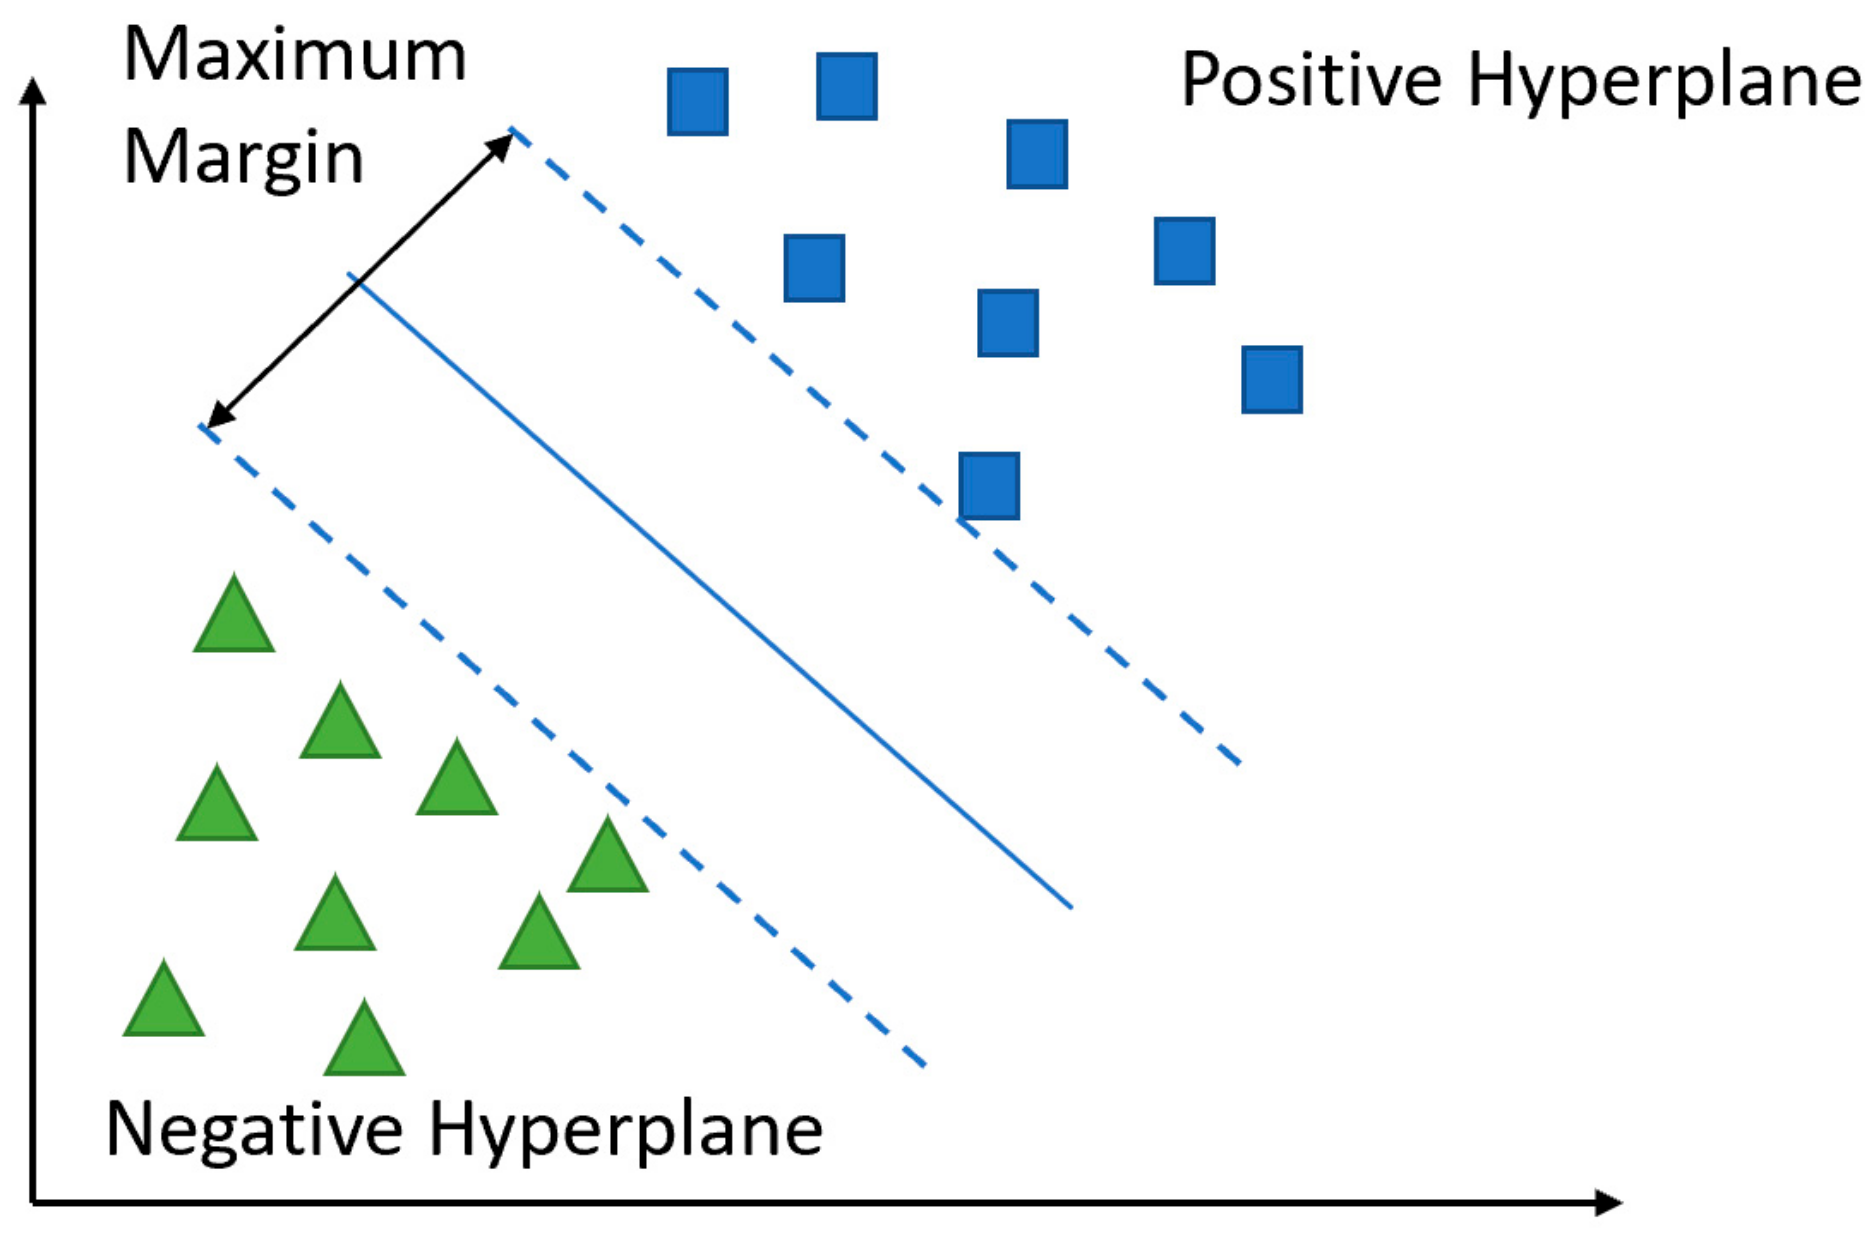

5.2.3. Support Vector Machine (SVM)